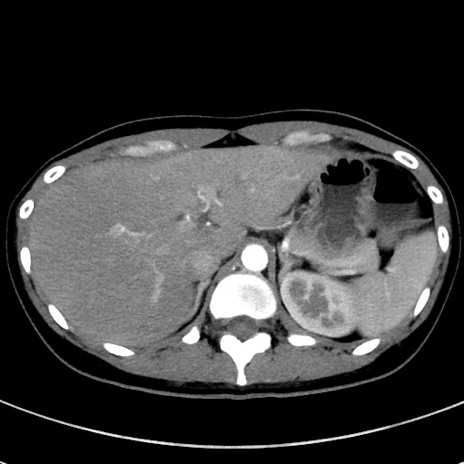

冠状断像

症例17(横断像)

【症例】20歳代女性

【主訴】嘔吐、下腹部痛

【現病歴】昨日夕食後に嘔吐し下腹部痛が出現。本日になっても嘔吐持続し改善しないため来院。

【身体所見】意識清明、BT 37.2℃、BP 108/67mmHg、腹部:平坦、やや硬、下腹部正中から右にかけて圧痛あり、反跳痛軽度あり、tapping pain(+)。

【データ】WBC 13600、CRP 14.94